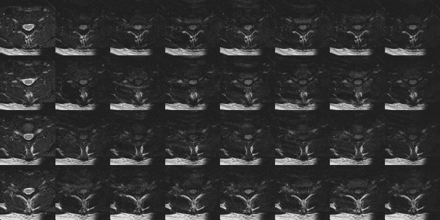

DTI data acquired during a mix of highly motional and quiescent periods of the cardiac cycle and strictly during the quiescent period are exemplified by the results shown in Figs 2 and 3, respectively. Three features are apparent from the acquired images. First, gating greatly reduces CSF-related ghosting in the T2-weighted, low b-value image used as a reference. Second, although ghosting of the spinal cord is not a prominent feature, the average intensity and the consistency of the cord appearance across sections and b-values is much higher in the images acquired entirely during the quiescent period. Finally, there is a notable ghosting of residual extraspinal tissues, particularly subcutaneous fat. To reduce the impact of ghosting from fat, subsequent DTI acquisitions were performed with fat suppression.

DTI data covering one vertebral body (4 sections) acquired entirely during the spinal cord quiescence for the same subject as Fig 2. Ghosting of CSF in the T2-weighted images is greatly reduced (left column), and the diffusion-weighted spinal cord signal intensity is more consistent. Some ghosting of subcutaneous fat is still apparent. Compared with Fig 2, the spinal cord is clearly seen in the average diffusion-weighted image (right column) for all sections.